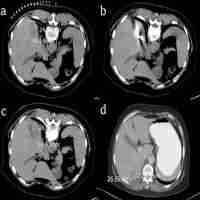

| Description | Radiofrequency ablation with systemic chemotherapy in the treatment of colorectal cancer liver metastasis: a 10-year single-center study Shuangyan Ou,1 Ruocai Xu,1 Ke Li,1 Yong Chen,1 Yi Kong,1 Hanchun Liu,1 Jianliang Li,1 Yongzhong Ouyang,2 Xiaoping Yu3 1Department of Hepatobiliary and Pancreatic Medicine, Hunan Cancer Hospital, Changsha City, Hunan Province, China; 2Department of Gastroduodenal Surgery, Hunan Provincial Cancer Hospital, Changsha City, Hunan Province, China; 3Department of Radiology, Hunan Cancer Hospital, Changsha City, Hunan Province, China Objective: To retrospectively evaluate the long-term efficacy and safety of radiofrequency ablation (RFA) with systemic chemotherapy (CT) in treatment of solitary liver metastasis after surgery for colorectal cancer (CRC). Methods: This single-center study was conducted at the Hunan Provincial Cancer Hospital from June 2006 to December 2015 with median follow-up time of 26 months. Percutaneous ultrasound-guided RFA was carried out on eligible patients with solitary liver metastasis after surgery for CRC. After a week, ablation status was confirmed by MRI. Post MRI, all patients received systemic CT with or without molecular-targeted therapy. Survival rate was evaluated and survival curve was constructed with Kaplan–Meier analysis. Log-rank test and Cox regression model were used for univariate and multivariate analysis, respectively, to determine the independent prognostic factors for survival rate. Results: A total of 109 eligible patients (mean age, 53.84±11.71; mean tumor mass diameter, 3.4+2.01 cm) were enrolled in this 10-year study. After RFA, 95 patients achieved complete ablation, and 14 patients achieved partial ablation, with median ablation time of 26 minutes (range: 12–120 minutes). The median survival time required for achieving complete and partial ablation was 56.0 and 19.0 months, respectively (P |